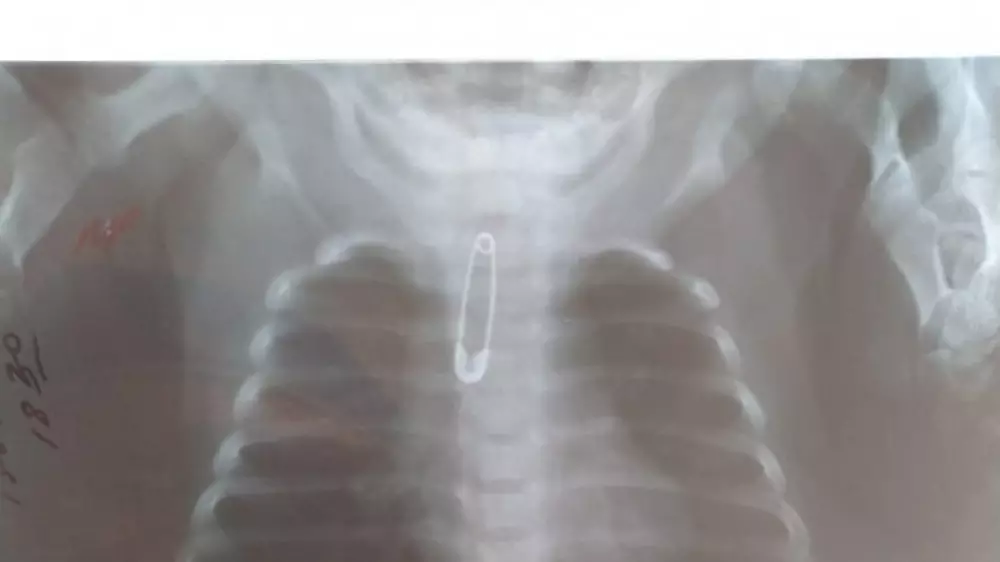

Шымкентте үш айлық сәбидің тамағына түйреуіш тұрып қалған. Дәрігерлер шұғыл ота жасап, баланы құтқарып қалды. Бұл туралы қалалық денсаулық сақтау басқармасы хабарлады, - деп хабарлайды Tengrinews.kz тілшісі.

Қауіпті затты алып тастау үшін шұғыл түрде аурухана хирургтері Әкім Төлкібаев, Нұрбол Қоянбаев, Берік Тотиков ота жасады.

"Ота кезінде фибробронхоскоп көмегімен түйреуішті алып тастады. Баланың жағдайы жақсы, хаттамаға сәйкес қажетті ем алады", - деді дәрігер Әкім Түлкібаев.